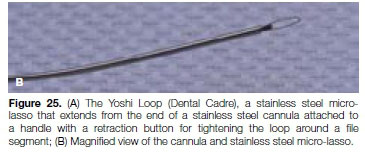

Typically, ledge formation occurs when stiff files with sharp inflexible cutting tips are used in a rotational motion in curved root canals. This common procedural error usually occurs on the outer side of the curvature when instruments are used aggressively, with exaggerated cutting during root canal instrumentation.6 Ledges are formed either within the original canal path or through creating a new false canal (Figure 1).